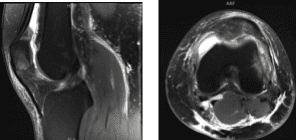

El paciente también presentó un resultado de resonancia magnética que mostró hallazgos acordes con reciente dislocación patuliana lateral transitoria con contusiones de impactación de la rótula inferomedial y del fémur distal anterolateral. Desgarro parcial en la unión rotuliana del retináculo medial. Derrame articular moderado. Quiste poplíteo parcialmente roto.

Resonancia magnética de rodilla izquierda sin contraste